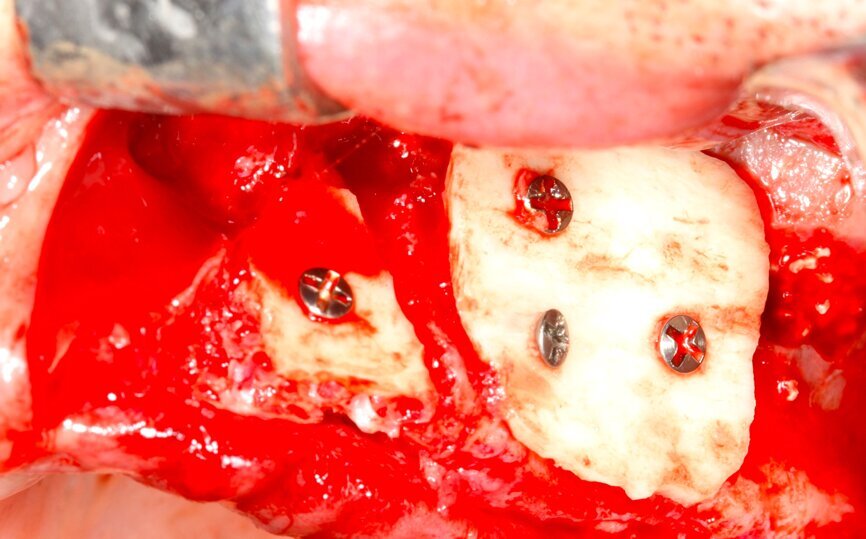

Fig. 15 Figura 15

5. Fijación del injerto previamente modelado al lecho con microtornillo de 1.5 a 2 mm de diámetro.

Fig. 16 Figura 16

6. Relleno de hueso particulado en la intersección entre el injerto óseo y el lecho receptor.

Fig. 17 Figura 17

7. Recubrimiento con una membrana reabsorbible o no reabsorbible para evitar la infiltración de tejido blando y garantizar la regeneración del defecto.

8. Fijación de la membrana con chinchetas para evitar su desplazamiento durante la reposición del colgajo.